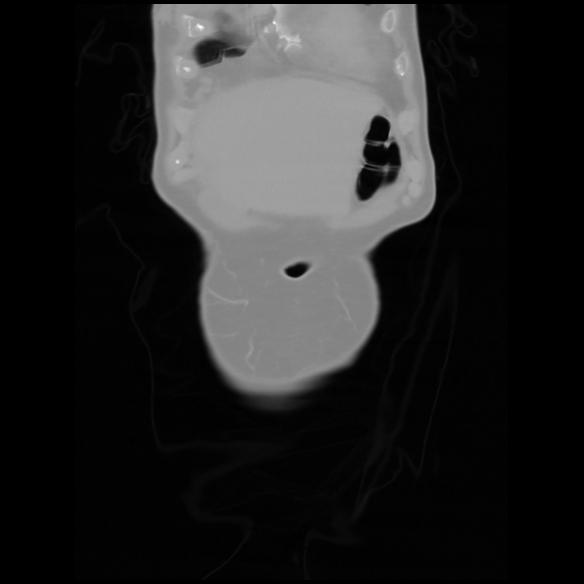

6 CUERPO,CE,Coronal,3.000,CUERPO,Coronal,